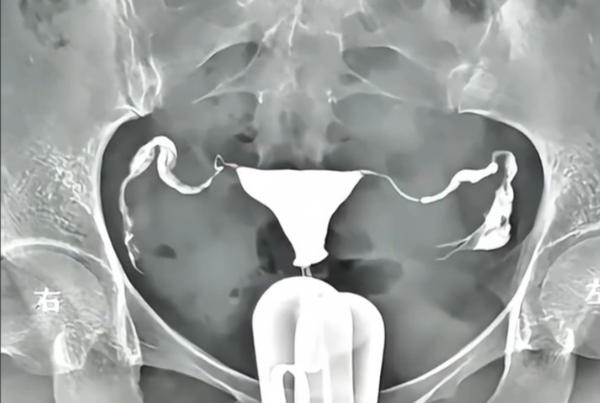

现在大家越来越重视生育健康,很多姐妹都会关心输卵管通不通。各种检查里,4D无痛输卵管造影因为看得清楚、几乎不疼、还没辐射,成了备孕人群的热门选择。不过技术听着高大上,大家最想问的还是:做一次到底要多少钱?为啥有的地方一千多,有的却要三四千?贵的就是好的吗?今天咱们就把4D无痛输卵管造影的价格这事儿,一次性聊明白。

那些特别便宜的,很可能是传统的X光输卵管造影,不仅疼,还有辐射;而那些特别贵的,往往捆绑了“套餐服务”,比如附带专家解读、术后理疗之类。所以咱们今天聊的4D无痛输卵管造影,特指用四维超声设备、配合特殊造影剂、并且采用无痛方式的检查。明确了这一点,下面咱们分几个小标题,把价格拆开揉碎了说。